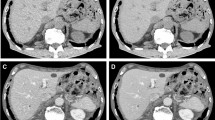

In the evaluation of the upper abdomen, the least subjective noise was observed in the ASiR-ABD images, followed by the DLIR-CHT images (2.94 ± 0.23 vs. 2.87 ± 0.26; p = .01). In terms of spatial resolution (liver sharpness evaluation), DLIR-CHT scored better than ASiR-ABD (2.60 ± 0.34 vs. 2.50 ± 0.30; p < .001). Distortion artifacts were more frequently observed on DLIR-CHT than on ASiR-ABD, but poor inter-reader agreement was found (ICC, 0.11). Distortion was noted on 17.0% (51/300) of the DLIR-CHT scans, but only one case was reported to affect the diagnostic value of the image (score 1, moderate to severe distortion, affecting diagnostic value; presented in Fig. 2), and others were interpreted as having a score of 2 (i.e., some distortions were recognizable but without diagnostic disturbance). There was no significant difference in beam hardening artifacts. ASiR-ABD showed the best overall image quality (3.04 ± 0.23), followed by DLIR-CHT (2.93 ± 0.20; p < .001). Detailed results are provided in Table 3, and representative cases are presented in Figs. 3, 4, and 5.

Examples of metastatic lesions covered on both deep learning–based image reconstruction–reconstructed chest CT (DLIR-CHT) and adaptive statistical iterative reconstruction–reconstructed abdominal CT (ASiR-ABD) images. a, b A metastatic nodule in the liver segment 2 (arrow) was more clearly demarcated on (a) DLIR-CHT images (required CTDIvol for the scan: 3.24 mGy) than on (b) ASiR-ABD images (CTDIvol: 7.06 mGy). c, d Peripancreatic soft tissue infiltration (arrows) and anterior peritoneal fat haziness (arrowheads) were clearly demonstrated on both (c) DLIR-CHT (CTDIvol: 3.09 mGy) and (d) ASiR-ABD (CTDIvol: 6.92 mGy) images